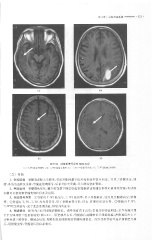

Page 309 - 医学影像诊断学